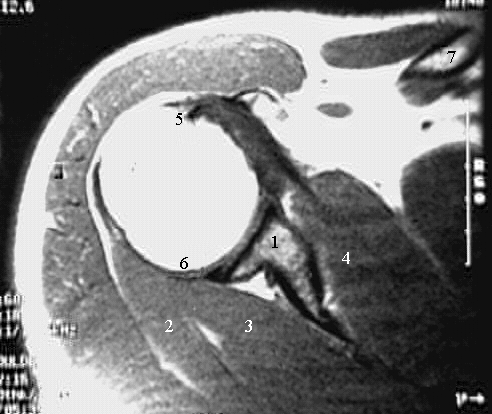

Upper Limbs: Shoulder MRI Zoom

1. Glenoid process

2. Teres minor m

3. Infraspinatus m

4. Subscapularis m

5. Tendon of long head of biceps m

6. Glenoid labrum.